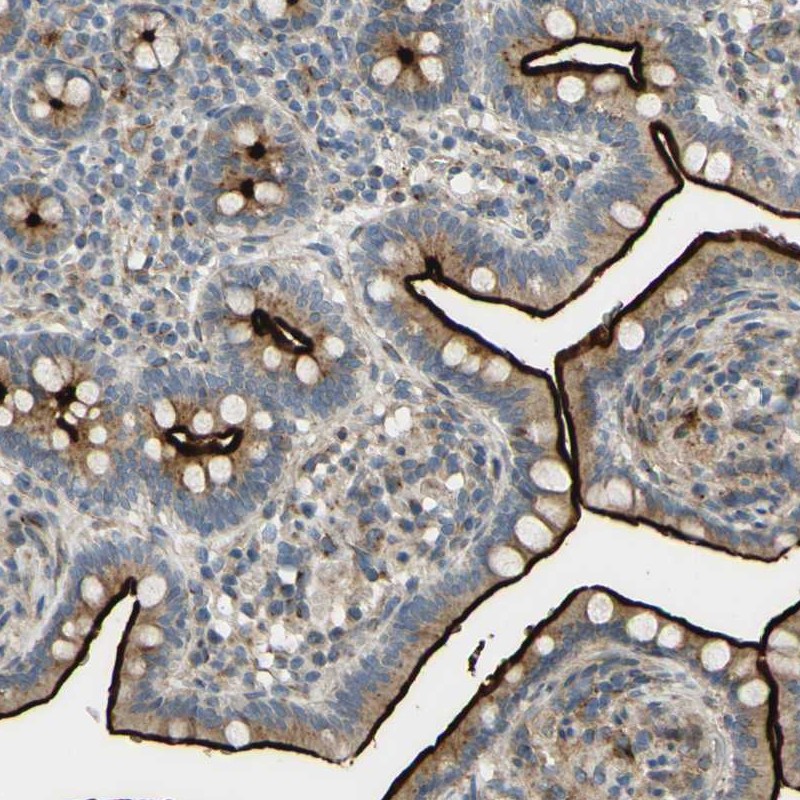

Immunohistochemical staining of human small intestine shows strong immunoreactivity along the luminal membrane and moderate cytoplasmic positivity in glandular cells.